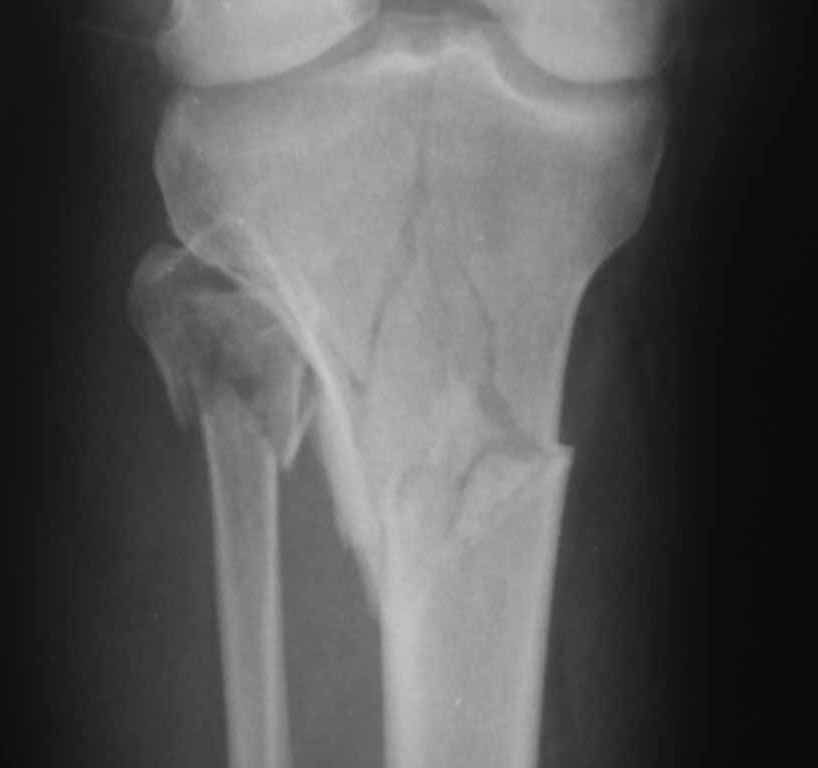

Двухколоннный перелом тибиал плато с вовлечением проксимального диафиза. Внутрисуставной компонент без смещения, и такой перелом можно лечить любым из описанных методов, о которых говорят наши коллеги.

Удобно аппаратом Илизарова или интрамедуллярным гвоздем. Гвозди не так сложно, как пугают, тем более Александр готов помощь с методичкой. Сперва надо установить компрессирующие шурупы на мыщелки. Давно отказались в пользу 3.5-4.0 мм кортикальных вместо толстых спонгиозных, потому что не доказаны преимущества толстых шурупов. Тонкие шурупы в субхондральной зоне смотрятся намного элегантнее, чем толстые 6.5.

Это мероприятие превращает перелом в простой диафизарный, который легко можно фиксировать гвоздем. Шурупы надо установить сзади предполагаемого места введения гвоздя.

Как понял, аппарат Илизарова не рассматривается предпочтительным для фиксации методом, хотя на фоне отека было бы идеальным для данного перелома. Для пластины требуется идеальная кожа, иначе наличие “суперсовременных имплантов” не поможет, и могут развиться серьезные осложнения.

Частая ошибка, когда фиксацию двух колонного перелома проводят одиночной пластиной, т.е с одной стороны, и такая фиксация не удерживает, происходит вторичноое смещение. Необходимо нейтрализовать второй пластиной или дополнительным наружным фиксатором.

Кстати, коллеги правы для уточнения характера перелома надо делать Компьютерную Томографию.